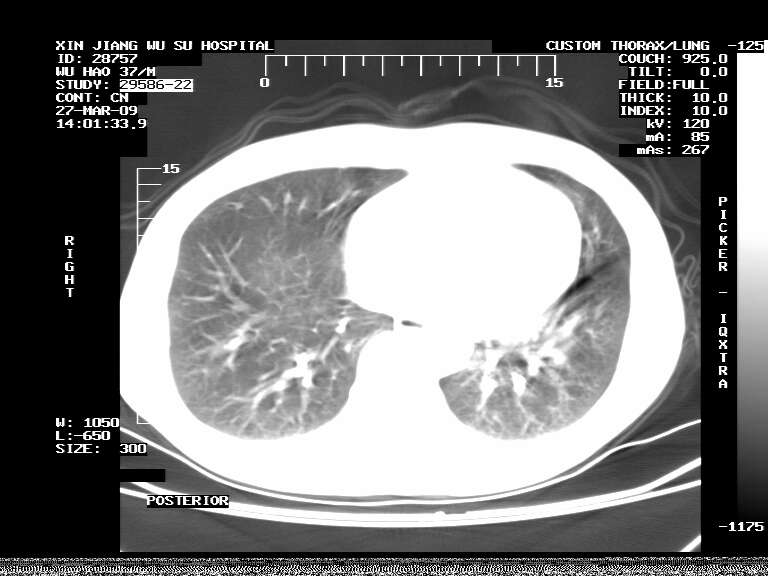

男,37岁,体检胸透发现阴影。

患者体检发现 无症状 左肺下叶占位,边缘模糊,可见血管聚束、分叶、胸膜牵拉,增强呈不均匀性强化。 首先考虑左肺下叶周围型肺癌,建议穿刺活检。

患者体检发现 无症状 左肺下叶占位,边缘模糊,可见血管聚束、分叶、胸膜牵拉,增强呈不均匀性强化。 首先考虑左肺下叶周围型肺癌,建议穿刺活检。支持!

左肺下叶见一结节病变,边缘欠清不光滑,与胸膜粘连且胸膜局限性增厚,注药后呈环形强化,动脉期壁呈明显点环状强化,静脉期壁强化减低,中心密度低无强化,灶周无明显的卫星灶和水肿区(晕征)---考虑周围性肺癌,不除外感染性病变,建议穿刺活检。

左肺下叶软组织病灶,密度较高,内见点状钙化,其周围见子灶,邻近胸膜扁平样增厚.c+病灶强化明显,中心强化弱.诊断:左肺下叶结核瘤.

周围有卫星灶,胸膜反应不明显,病灶中心有坏死。建议先抗结核治疗后,短期复查

左肺下叶大片实变影,内靠胸膜见不规则更高密度结节灶,边缘强化,相邻胸膜增厚,胸膜下脂肪线存在。考虑炎症,结核可能。